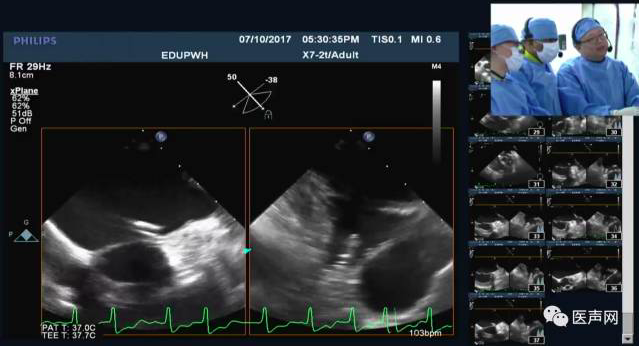

不忘初心 共享学术-手术演示分享经验

在梦想的追逐过程当中,APCASH 的角色发生了变化。APCASH成立之初以手术演示和欧美专家授课为主,仅仅是作为一个学习西方先进技术的窗口。随着亚洲先心病介入治疗的发展和医生水平的提高,会议规模逐渐增加,更多地成为经验分享及交流会议。但在这十年历练的过程中,APCASH不忘初心,始终以共享知识为目的。